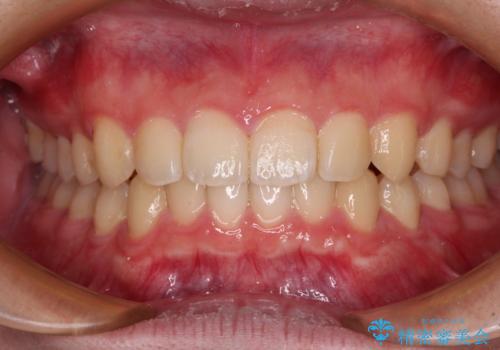

極端な上下前歯の開咬を改善 オープンバイトのインビザライン矯正

- 上下前歯の隙間を気にして来院された患者様です。

開咬の治療は、前歯を閉じるように動かすとともに、上下臼歯を圧下(骨内にめり込ませる)させることで進めて行きます。

インビザラインは臼歯の圧下を効果的に行えるため、インビザラインを用いて矯正治療を行うこととしました。

治療前に、いくらインビザライン矯正がオープンバイトを得意としているとは言え、さすがに限界があるだろうと思っておりましたが、前歯でレタスが噛めるまで改善することができました。

顔の印象も大きく変わり、患者様には大変満足していただきました。